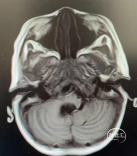

术前头部MRI

右侧桥小脑角区可见一不规则等T1、等-T2信号灶,大小约46*51*55mm3边界欠清,病灶突入四脑室内,第四脑室受压变窄,强化明显。